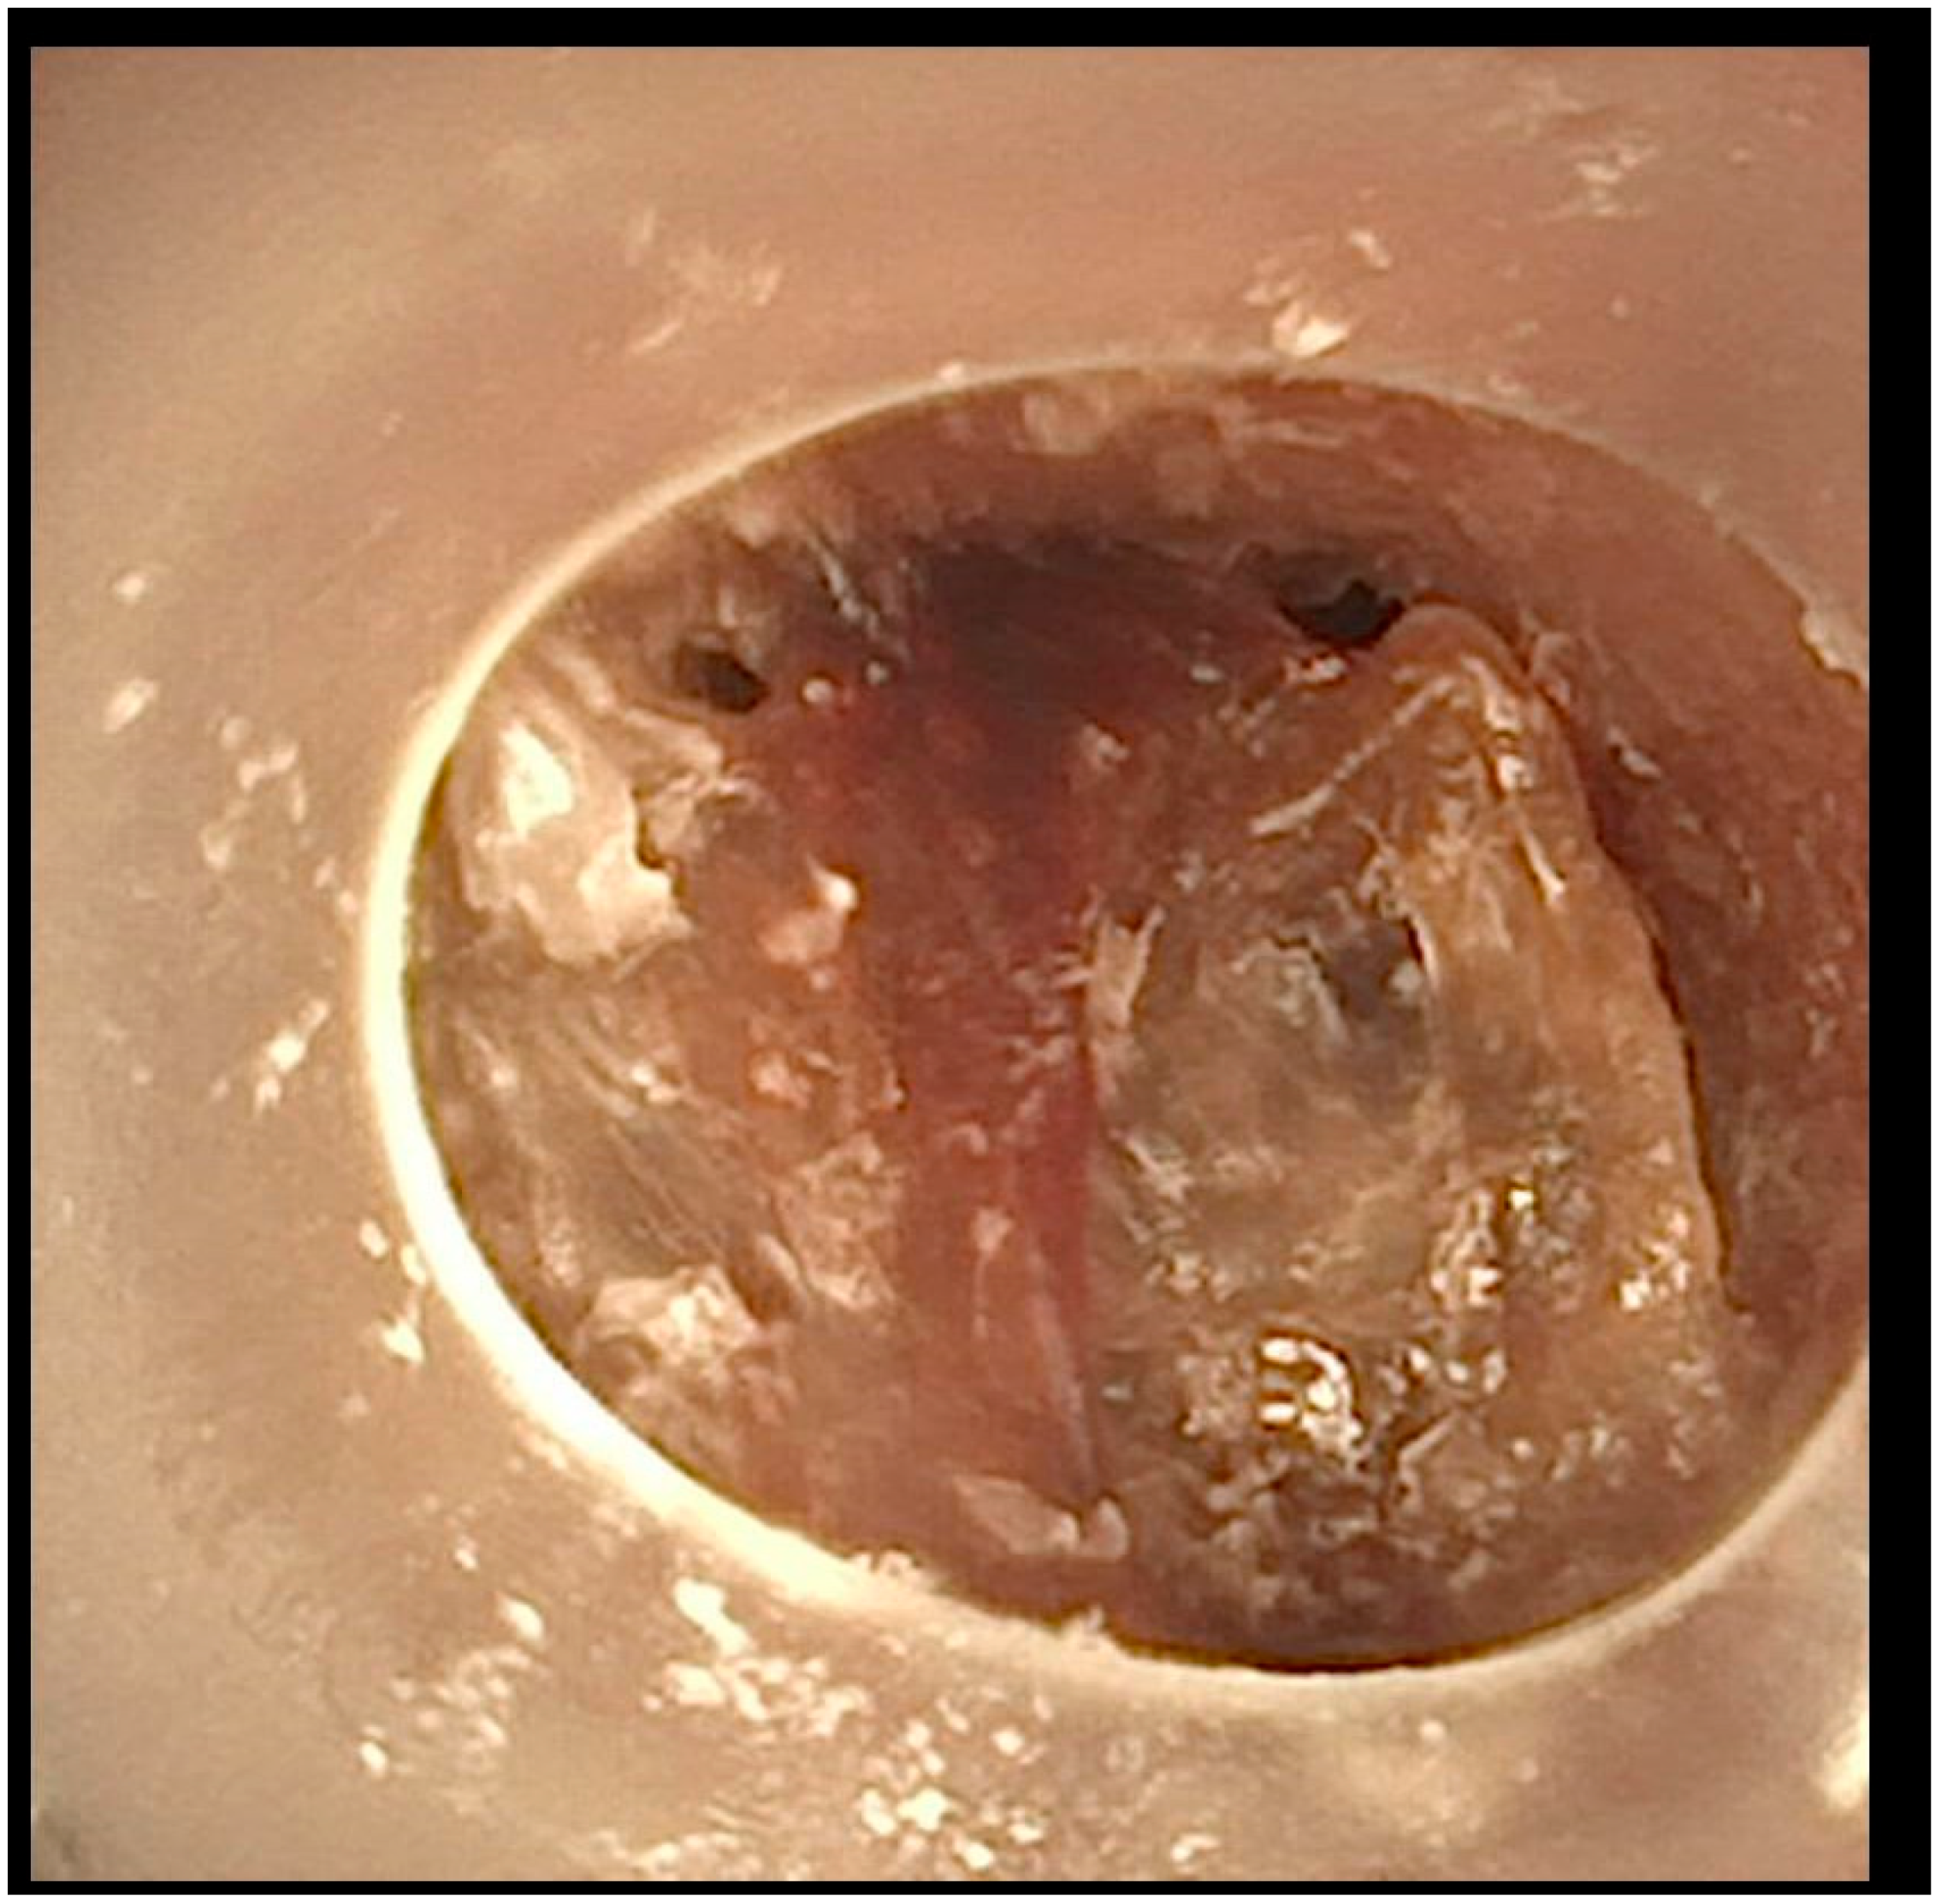

A flexible bronchoscopic examination at our facility showed extensive granulomatous tissue distal to the tracheostomy tube, with significant inflammation in the distal trachea and bronchi (Figure 2).

After this comprehensive approach, the patient’s tracheal obstruction episodes resolved, and the granulomatous tissue showed significant regression (Figure 3).

Figure 2. Tracheoscopic visualization at the distal end of the tracheostomy cannula. The cannula abrades the granuloma.

Figure 3. Image taken after 3 months of specific cannula management.